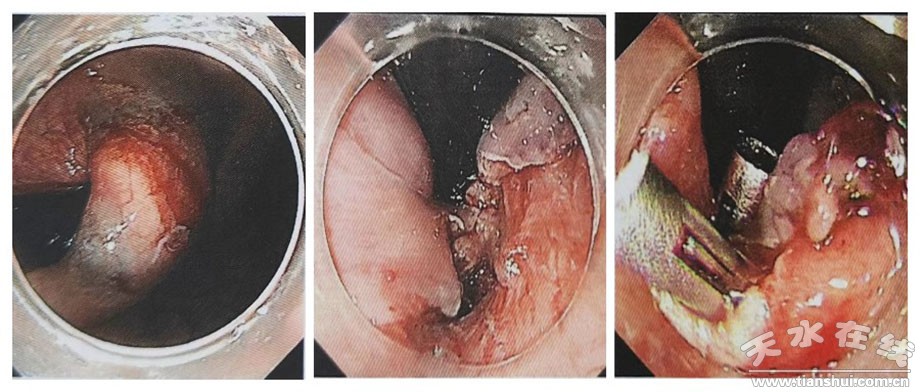

今年52歲的劉女士,因腹部不適就診首都醫(yī)科大學(xué)北京同仁醫(yī)院,行胃鏡檢查,發(fā)現(xiàn)賁門翻轉(zhuǎn)位可見似黏膜下腫樣隆起,約2.0*1.5cm;超聲內(nèi)鏡提示病變位于胃壁第四層,偏低回聲,測量大小約3.5*1.0cm。

7月4日13:30在市一院內(nèi)鏡中心和麻醉科的協(xié)助下,進(jìn)行全身麻醉+氣管插管,手術(shù)過程中,在蘭大一院姬瑞主任醫(yī)師的指導(dǎo)下,消化內(nèi)科茍金平主任醫(yī)師、贠嘉威主治醫(yī)師、張云主治醫(yī)師及內(nèi)鏡室護(hù)士的協(xié)調(diào)配合下,在內(nèi)鏡下使用Dual-knife切開腫瘤表面黏膜層,暴露白色瘤體,后沿黏膜下層剝離瘤體,并予以圈套器、活檢鉗輔助牽引完整挖除瘤體,剝離過程中出現(xiàn)穿孔,予以9枚鈦夾封閉創(chuàng)面。患者右側(cè)胸壁、顏面部可觸及捻發(fā)感,遂啟動多學(xué)科協(xié)作(MDT),請胸外科、超聲科、放射科、重癥醫(yī)學(xué)科等多學(xué)科專家術(shù)中會診,考慮皮下氣腫。術(shù)中嚴(yán)密觀察患者,生命體征平穩(wěn),手術(shù)成功,實現(xiàn)了以最小創(chuàng)傷達(dá)到最佳治療效果的目的。為保證患者安全,術(shù)后轉(zhuǎn)重癥醫(yī)學(xué)科觀察。術(shù)后2小時,患者順利拔出氣管插管,神志清楚,病情平穩(wěn),未訴腹痛、腹脹,無嘔血、黑便。術(shù)后15小時轉(zhuǎn)回消化內(nèi)科普通病房進(jìn)行術(shù)后恢復(fù)治療,目前患者情況良好,近日準(zhǔn)備出院。